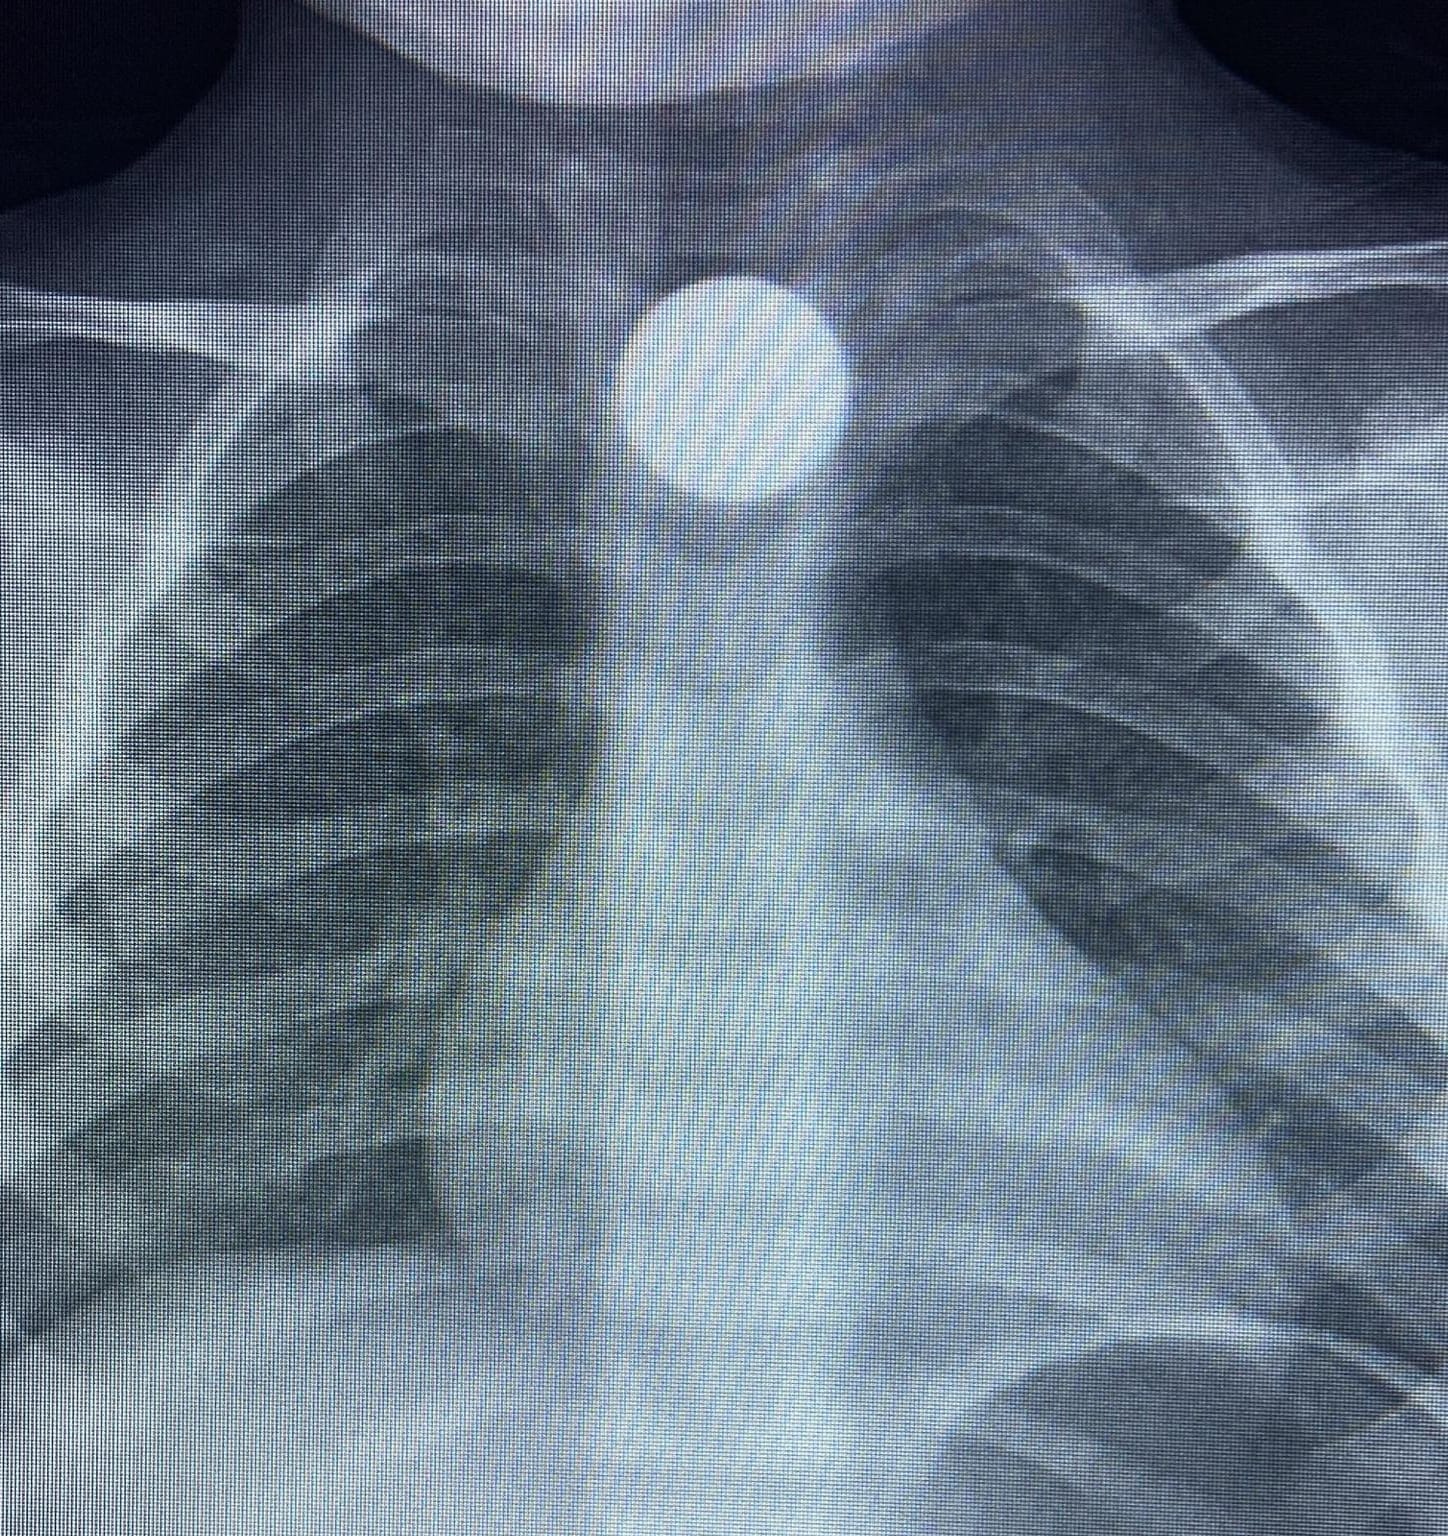

Yapılan tetkiklerde yemek borusunda takılı kalan madeni para görüldü. Çocuk ilk tedavinin ardından ambulansla Bursa Yüksek İhtisas Eğitim Ve Araştırma Hastanesi'ne sevk edildi.